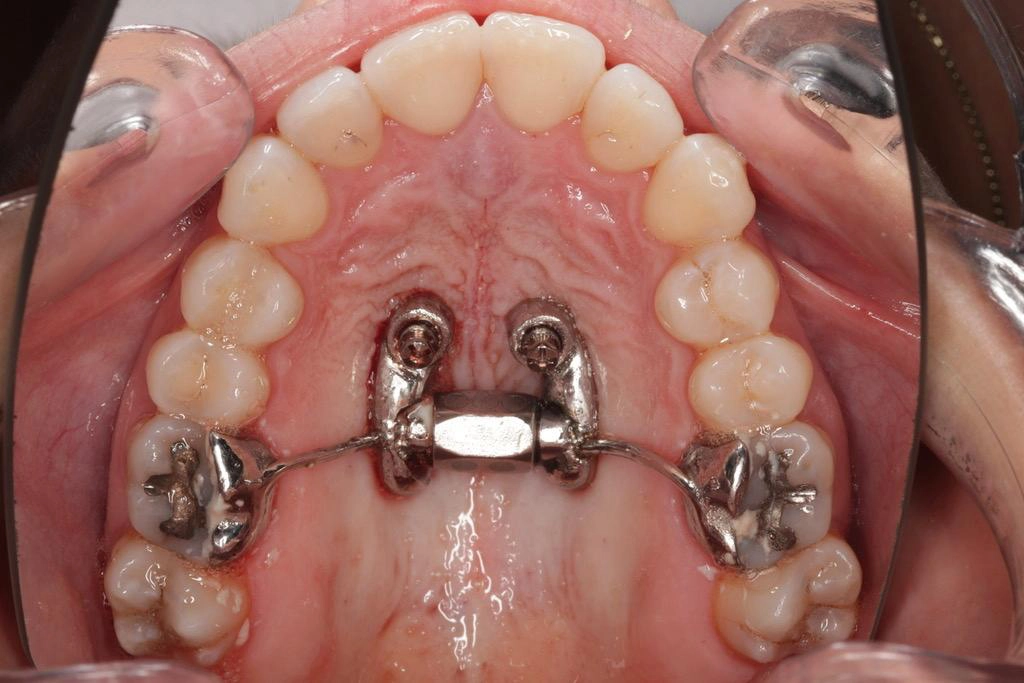

Una vez realizado el diagnóstico pasamos a la planificación donde el CBCT se integra con el escaneado intraoral mediante un archivo STL, creando un modelo digital completo en el que se planifica la trayectoria y ubicación ideal del MARPE.

Microtornillos y bicorticalidad: decisión biomecánica (no estética)

La elección de los microtornillos juega un papel determinante en el éxito del MARPE. Habitualmente se emplean diámetros iguales o superiores a 1.6 mm y longitudes que faciliten alcanzar la bicorticalidad (12-16mm) que implica atravesar ambas corticales para lograr estabilidad primaria elevada, algo especialmente relevante en pacientes adultos, donde la resistencia ósea aumenta. La bicorticalidad reduce el riesgo de aflojamiento, distribuye mejor las cargas y mejora la predictibilidad de la apertura sutural. Por ello, seleccionar el microtornillo adecuado no es una cuestión estética del dispositivo, sino una decisión biomecánica crítica basada en las mediciones realizadas en el CBCT.